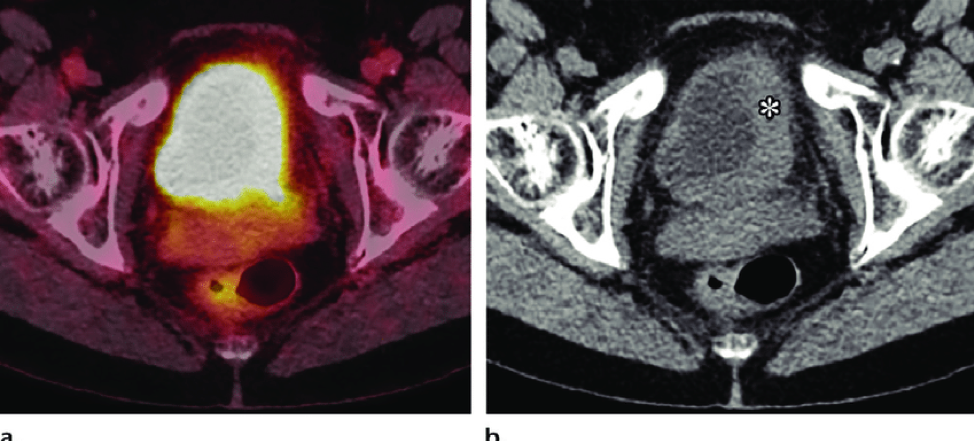

Dive into the stunning world of abstract Renal Cancer Pet/ct with vast arrays of imaginative images. highlighting the innovative use of photography, images, and pictures. ideal for modern art and design. Browse our premium Renal Cancer Pet/ct gallery featuring professionally curated photographs. Suitable for various applications including web design, social media, personal projects, and digital content creation All Renal Cancer Pet/ct images are available in high resolution with professional-grade quality, optimized for both digital and print applications, and include comprehensive metadata for easy organization and usage. Our Renal Cancer Pet/ct gallery offers diverse visual resources to bring your ideas to life. Time-saving browsing features help users locate ideal Renal Cancer Pet/ct images quickly. Reliable customer support ensures smooth experience throughout the Renal Cancer Pet/ct selection process. Cost-effective licensing makes professional Renal Cancer Pet/ct photography accessible to all budgets. Professional licensing options accommodate both commercial and educational usage requirements. Diverse style options within the Renal Cancer Pet/ct collection suit various aesthetic preferences. The Renal Cancer Pet/ct collection represents years of careful curation and professional standards. Each image in our Renal Cancer Pet/ct gallery undergoes rigorous quality assessment before inclusion. Multiple resolution options ensure optimal performance across different platforms and applications.